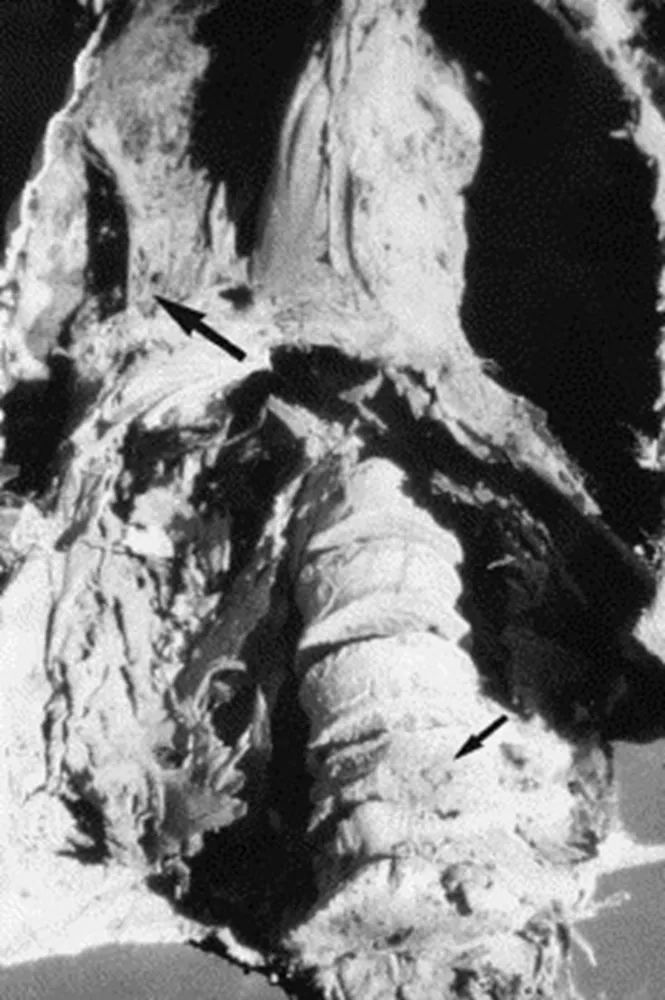

结核病是一种伴随着整个人类的历史的古老疾病,甚至还可以进一步追溯到史前时期。目前认为非洲东部可能是人类结核病的发源之地,早在五千年前的古埃及就存在关于结核病的相关记载,科学家们还在木乃伊身上发现了结核病导致的典型的骨骼异常,并在残留的身体组织中找到了病原体的DNA[3]。

箭头处所示木乃伊体内由于结核病造成的破坏

图源:参考文献3